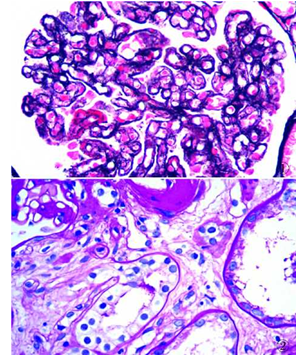

2.2染色石蜡切片经GS染色套液处理后,11种特殊染色结果稳定,组织结构清晰,着色部位准确,色泽艳丽分明 (图1 -4),且染色时间缩短,完全可以替代传统染色试剂。

图1肾小球************袢僵硬、基膜弥漫性增厚,外周袢分层、双轨状,内皮下、上皮侧大量嗜复红物沉积,PASM-Masson染色

图2肾小球入球小动脉管壁及肾小管基膜透明样变性,PAS染色

本科室进行的十几种特殊染色中,经格林GS新型环保试剂处理,糖原、淀粉样物质、网状纤维、含铁血黄素、抗酸杆菌等均取得较好的固定效果,特殊染色结果色彩分明,对比清晰,能够清楚显示肾小球************基膜病变、肾间质小动脉的玻璃样变性、骨髓穿刺组织中网状纤维分布、甲状腺髓样癌中沉积的淀粉样物质等,其染色效果与传统制片染色方法相当,能够很好应用于病理诊断。